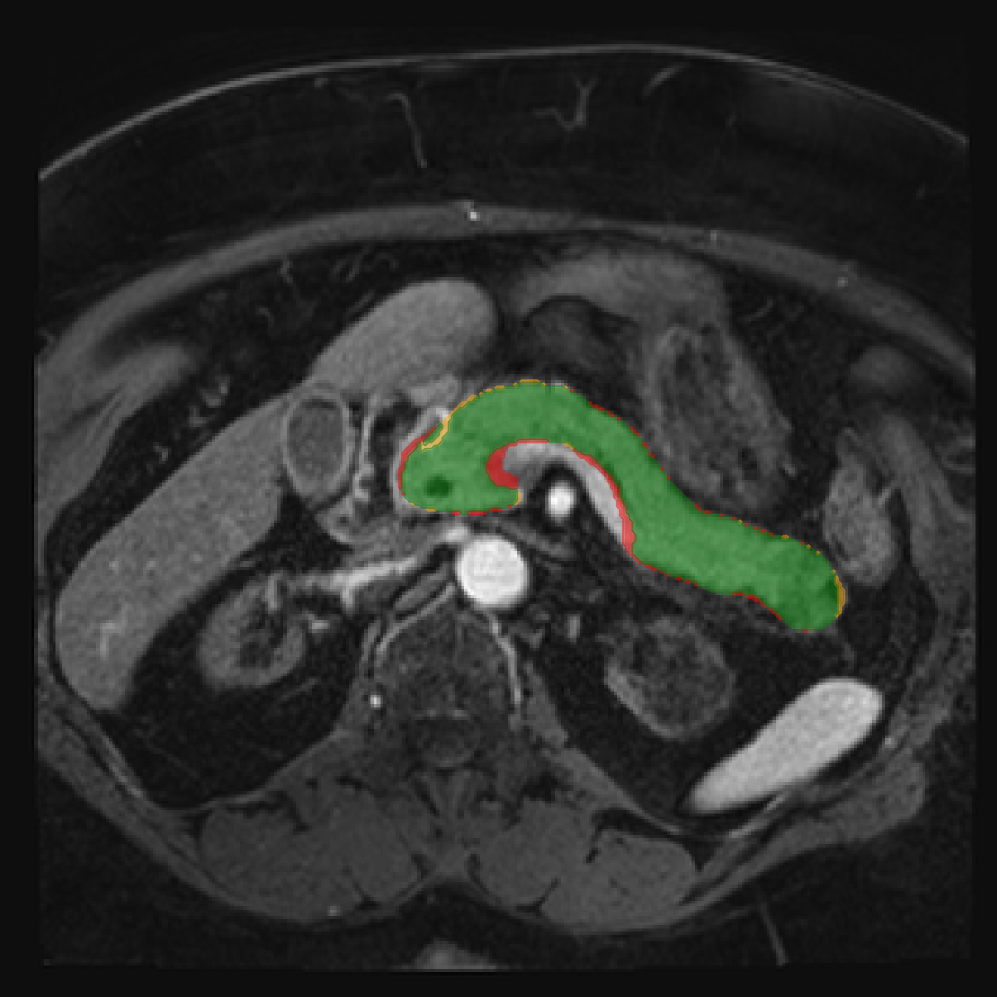

Accurate pancreas segmentation is a critical prerequisite for precise cyst analysis and classification. Recently, we developed PanSegNet [zhang2025large], a novel segmentation architecture incorporating linear self-attention layers [zhang2022dynamic] within the nnUNet framework [isensee2021nnu] to enhance global information modeling capabilities while maintaining computational efficiency (Fig. 1). PanSegNet demonstrated exceptional segmentation performance across both T1W and T2W modalities, achieving mean dice scores of 86.817.30% and 89.626.38%, respectively (Table 1, Fig. 2b-c). This performance significantly exceeded that of Swin-UNETR [hatamizadeh2021swin], one of the most used state-of-the-art transformer-based medical segmentation models, which achieved dice scores of 79.091.40% and 76.290.66% for T1W and T2W, respectively (). In this study, we integrated PanSegNet into our Cyst-X engine along with a classifier for risk prediction. In Section 2.2, we show that the choice of segmentation model affects the classification results. The performance advantage of PanSegNet was consistent across all seven medical centers, demonstrating robust generalization despite variations in imaging protocols and equipment (Table 1). This cross-institutional reliability is particularly important for clinical applications, where model performance must remain consistent regardless of imaging site or acquisition parameters.

2.2.1 Importance of accurate pancreas segmentation in classification

To assess the importance of accurate pancreas segmentation in classification, we evaluated how different ROI sources affect DenseNet-121’s performance. Specifically, we compared classification results using ROIs generated by PanSegNet and Swin-UNETR, both under centralized learning, against a baseline using radiologist-defined ROIs. As shown in Table 2, using PanSegNet’s masks resulted in only a modest performance decline, reflecting its strong segmentation quality. In contrast, Swin-UNETR led to a more substantial drop, demonstrating that inferior segmentation can directly compromise classification. For 3-class classification, the mean AUC dropped from 75.59% (radiologist ROI) to 72.26% with PanSegNet, and further to 66.95% with Swin-UNETR on T1-weighted images. On T2-weighted scans, the AUC declined from 81.09% to 74.18% (PanSegNet) and to 69.63% (Swin-UNETR). A similar trend was observed in 2-class classification: on T1W, AUC dropped from 78.13% to 74.84% (PanSegNet) and 70.20% (Swin-UNETR); on T2W, from 82.37% to 77.01% and 68.92%, respectively. These results emphasize that accurate segmentation—particularly via PanSegNet—is not only essential for volume estimation but also critical to preserving downstream classification performance in the Cyst-X pipeline.